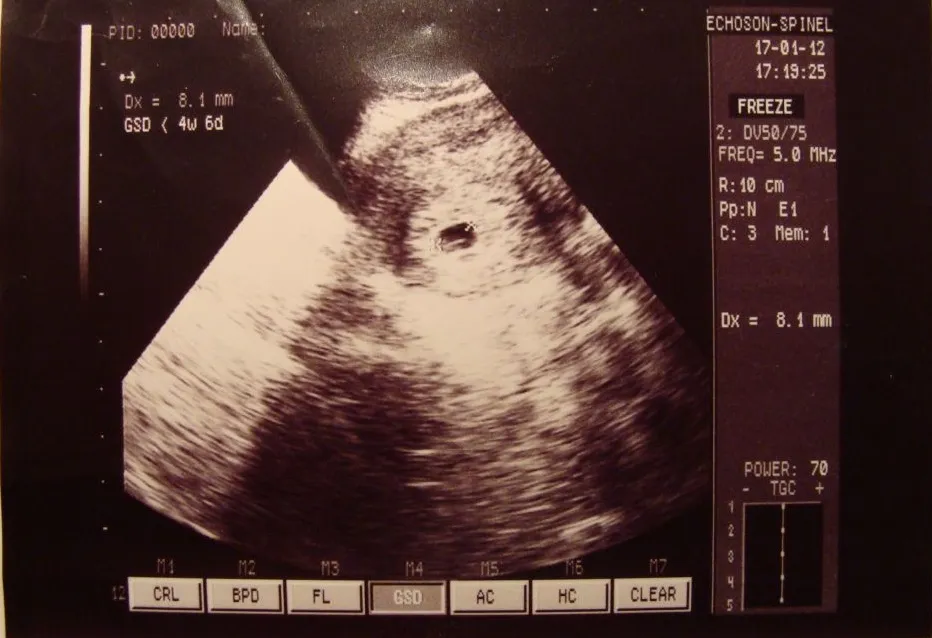

Pęcherzyk ciążowy: Bezpieczne schronienie dla rozwijającego się dziecka

Pęcherzyk ciążowy w 5 tygodniu to kluczowa struktura otaczająca zarodek. Składa się z trzech warstw: zewnętrznej, środkowej i wewnętrznej, każda pełniąca istotną rolę w ochronie i odżywianiu rozwijającego się dziecka. Jego ściany są cienkie i elastyczne, co umożliwia wzrost wraz z powiększającym się zarodkiem.

Funkcja pęcherzyka ciążowego jest niezwykle ważna. Zapewnia on nie tylko fizyczną ochronę, ale także dostarcza składniki odżywcze niezbędne do prawidłowego rozwoju dziecka. Dodatkowo, pęcherzyk ciążowy pomaga w utrzymaniu odpowiedniej temperatury i wilgotności dla optymalnego wzrostu zarodka.